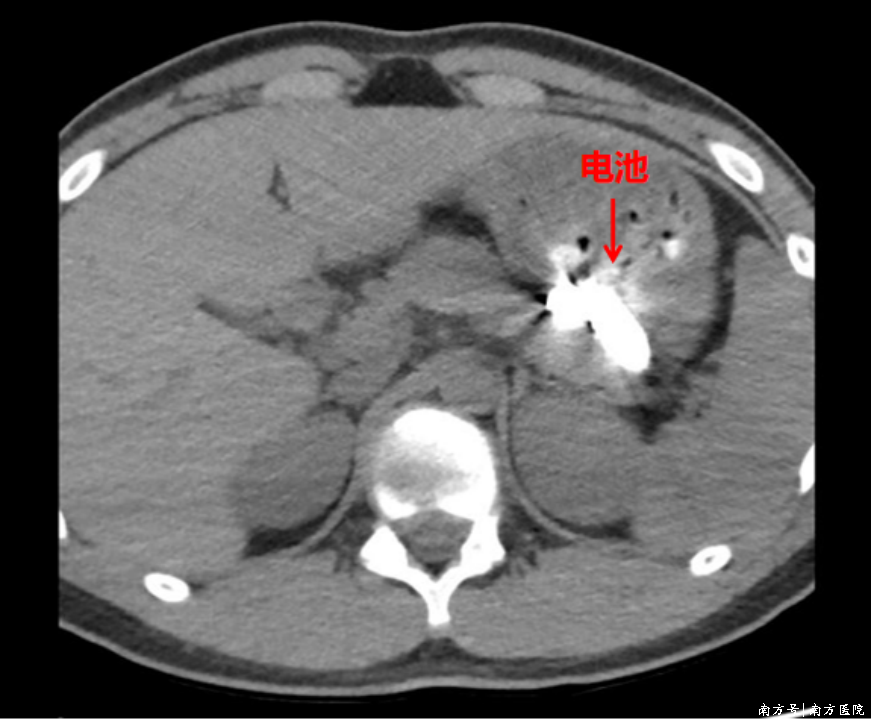

“吞服异物后不能贸然进镜,必须先明确异物位置和身体损伤情况。”医生解释,若不清楚电池位于食管、胃还是肠道,也不了解电池是否已漏液、是否腐蚀黏膜,贸然操作可能加重损伤,甚至引发食管或胃壁穿孔,风险极高。随后,医生第一时间为患者安排CT检查,明确异物位置。

影像结果显示,两枚电池均位于患者胃腔中,大香蕉大香蕉大香蕉但新的难题随之而来——患者胃内有大量未消化的食物,两枚小小的电池被深埋在食物残渣之中,视野极度浑浊。更棘手的是,由于患者禁食时间不足,无法立即进行麻醉,只能在完全清醒的状态下接受普通胃镜操作,这无疑增加了操作难度和患者的不适感。